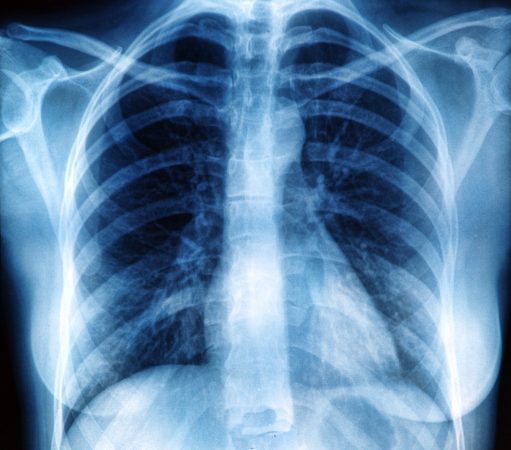

Рентген здоровых легких: примеры снимков и советы

Раздел: Сокровищница опыта